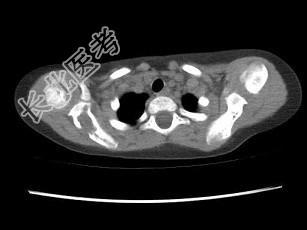

单项选择题女,2岁半, 无痛性右肩部肿块,结合图像, 最可能的诊断是 ( )

A、朗格汉斯细胞增多症

B、尤文肉瘤

C、骨髓瘤

D、霍奇金病

E、淋巴瘤